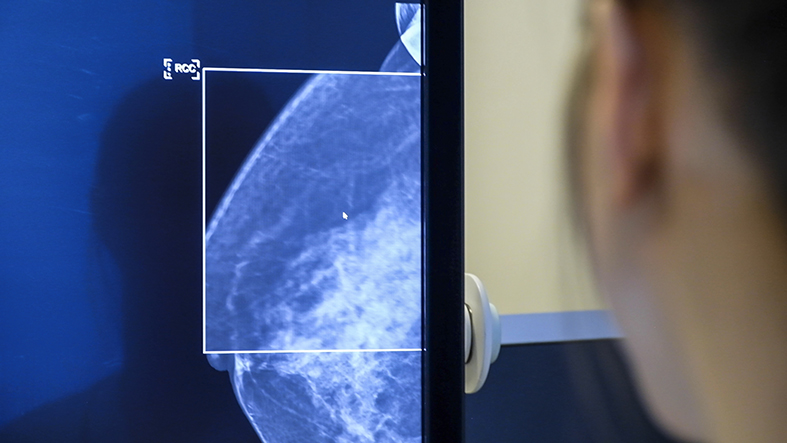

Röntgenbild av bröst på skärm från mammografiscreeing